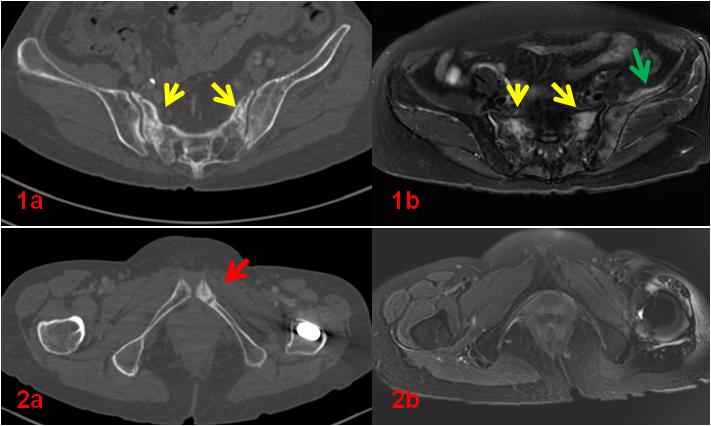

老年女性,1年前因直腸惡性腫瘤于外院行放射治療,此次常規(guī)復(fù)查平掃CT示骶骨及左側(cè)恥骨密度不均勻,左側(cè)恥骨骨質(zhì)斷裂;平掃M(jìn)R示雙側(cè)骶骨翼、左側(cè)髂骨及左側(cè)恥骨異常信號(圖1、2);為進(jìn)一步明確診斷行全身骨顯像ECT檢查(圖3)。

圖1、2初診CT、MR影像。CT示骶骨密度不均勻增高(1a,黃箭),同部位MR顯示壓脂信號增高(1b,黃箭),同時顯示左側(cè)髂骨及周圍軟組織壓脂信號增高(1b,綠箭);左側(cè)恥骨骨質(zhì)斷裂(2a,紅箭)。